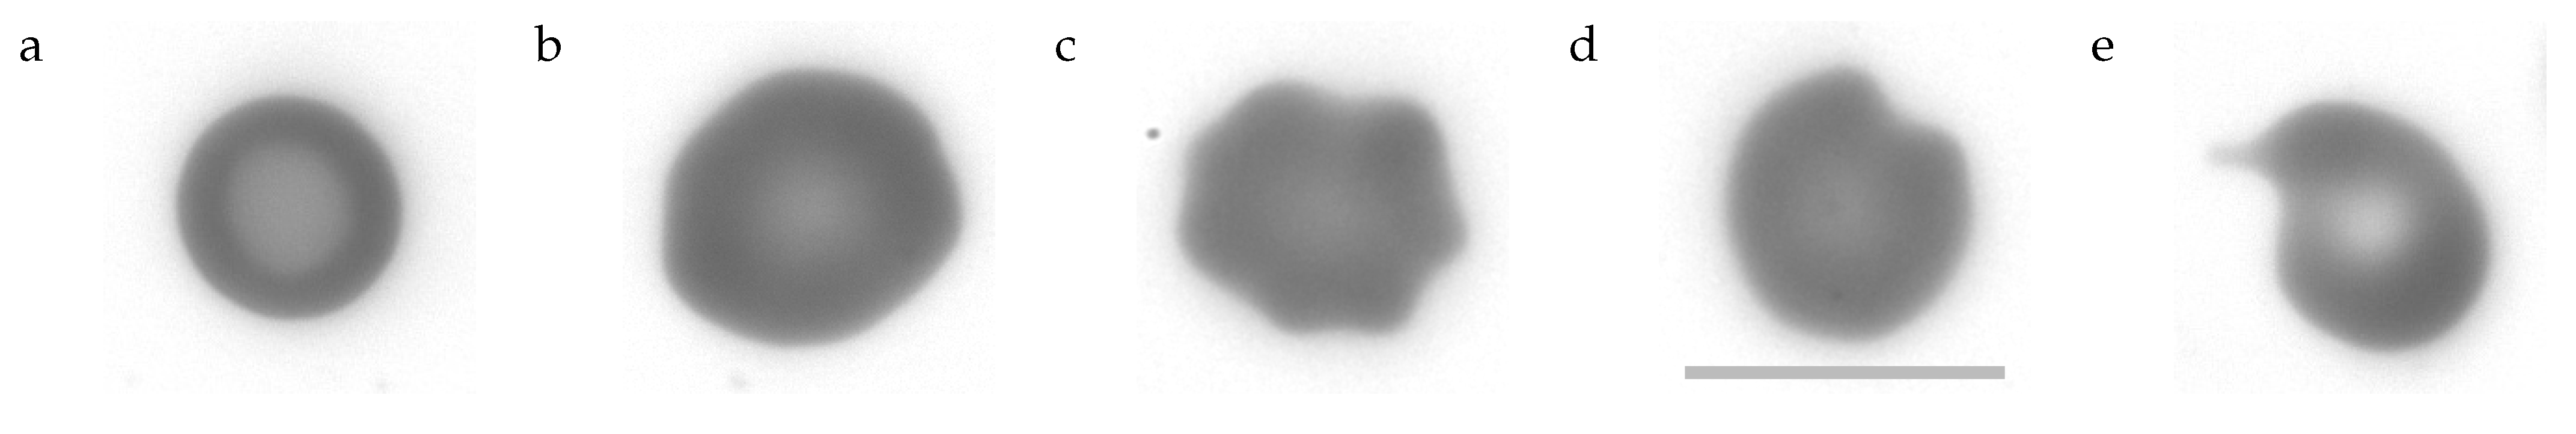

- Stomatocytes

- can be described as cup-shaped RBCs (cf. Figure 1 last image). Their profile of GVs shows two minima and a maximum just as the profile of biconcave discocytes. However, what appears to be the rim or dimple in the profiles is actually the wall or bottom of the cup, respectively. The profile is less curved in the “dimple” region and the transition from the “rim” to the “dimple” is abrupt unlike in discocytes. Examples of the filtering procedure are shown in Supplementary Section S5. A typical stomatocyte is shown in Figure 4a.

- Echinocytes type 1 (E1)

- oriented edge-on and sectioned microscopically through the center appear biconcave. In the face-on orientation, their outline is wavy. An example of the filtering procedure is shown in Supplementary Section S6. A typical E1 is shown in Figure 4b.

- Echinocytes type 2 (E2)

- are similar to E1 in that their overall shape is flat and their outline is wavy in the face-on orientation. In addition, E2s show spicules (cf. Figure 1 first image) or bumps (cf. Figure 1 second image) extending away from the mid-plane. In the present experiments these bumps are recognized as a local increase in GV. An example of the filtering procedure is shown in Supplementary Section S6. A typical E2 is shown in Figure 4c.

- Pitting type 1 (P1):

- The outline of some of these RBCs presented a single indentation in the face-on orientation. In others the curvature of the outline was zero or negative in places (the outline of a circle is defined as positive).The nomenclature (pitting) relates to the suggested origin of these shape (Section 4.7.2 and Section 4.7.3). A prominent example is shown in Figure 4d and all P1s found are shown in Supplementary Figures S10 and S11.

- Pitting type 2 (P2):

- Some of these RBCs showed a tongue protruding from the body of the RBC. Others were unusually small. A prominent example is shown in Figure 4e and all P2s found are shown in Supplementary Figure S12.